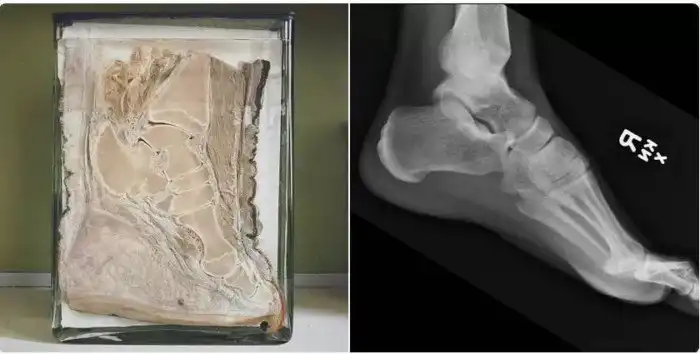

Нога слона и человека